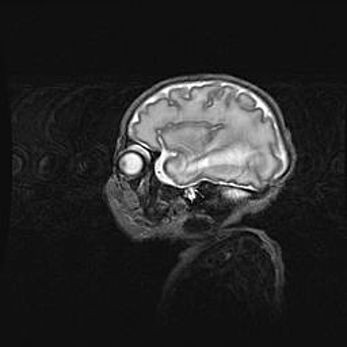

Подострая гематома правой гемисферы мозжечка.

Наружная гидроцефалия.

Возраст: 15 дней

Вес: 3100 г

Пол: женский

Окружность головы: 37 см

Срок гестации: 35-36 недель

При открытой наружной форме гидроцефалии у новорожденных расширяются и переполняются субарахноидные пространства.

Кровоизлияния в мозжечок имеют две клинико-анатомические формы: полушарные гематомы и кровоизлияния в червь.

К появлению этой патологии может привести: повреждения головного мозга, возникающие в результате асфиксии и гипоксии плода при беременности, или травмы во время родов. Редко гематома мозжечка может быть результатом первичной коагулопатии и сосудистой мальформации, диссеминированном внутрисосудистом свертывании, изоиммунной тромбоцитопении.